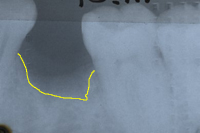

Abb. 6 zeigt den Verlust eines unteren Milchzahnes bei einem 26 Jahre jungen Patienten. Gesunde Nachbarzähne veranlassen uns, ein Implantat vorzuschlagen und auf eine Brücke zu verzichten, welche das Beschleifen der Nachbarzähne nötig gemacht hätte. Stark erschwerend ist allerdings, dass im Röntgenbild von Abb. 6 ein grosser Knochenkrater sichtbar ist.

Abb. 7 zeigt, wie das Knochentransplantat aus dem Kinn fixiert wird, um den Knochenkrater zu füllen. Nach viermonatiger Einheilung (Abb. 8) setzen wir das Implantat.

| Ursprünglicher Verlauf des Kieferkammes | |

| Neuer Verlauf des Kieferkammes | |

| Gebiet zwischen gelber und grüner Linie: Knochenaufbau | |

Im Röntgenbild von Abb. 9 sieht man, dass dreieinhalb Jahre später absolut perfekte Knochenverhältnisse ums Implantat herrschen. Abb. 10 zeigt die klinische Situation dreieinhalb Jahre nach dem Zementieren der Implantatkrone.